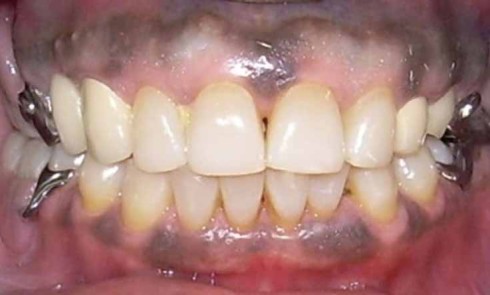

Article réservé à nos abonnés Les prothèses amovibles partielles métalliques sont-elles traumatisantes pour les dents supports ?

En raison de l’augmentation de l’espérance de vie, la proportion de la population partiellement édentée est plus importante (1). Plusieurs...